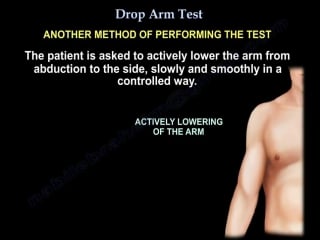

Rotator cuff tear,drop arm test everything you need to know dr nabil ebrah